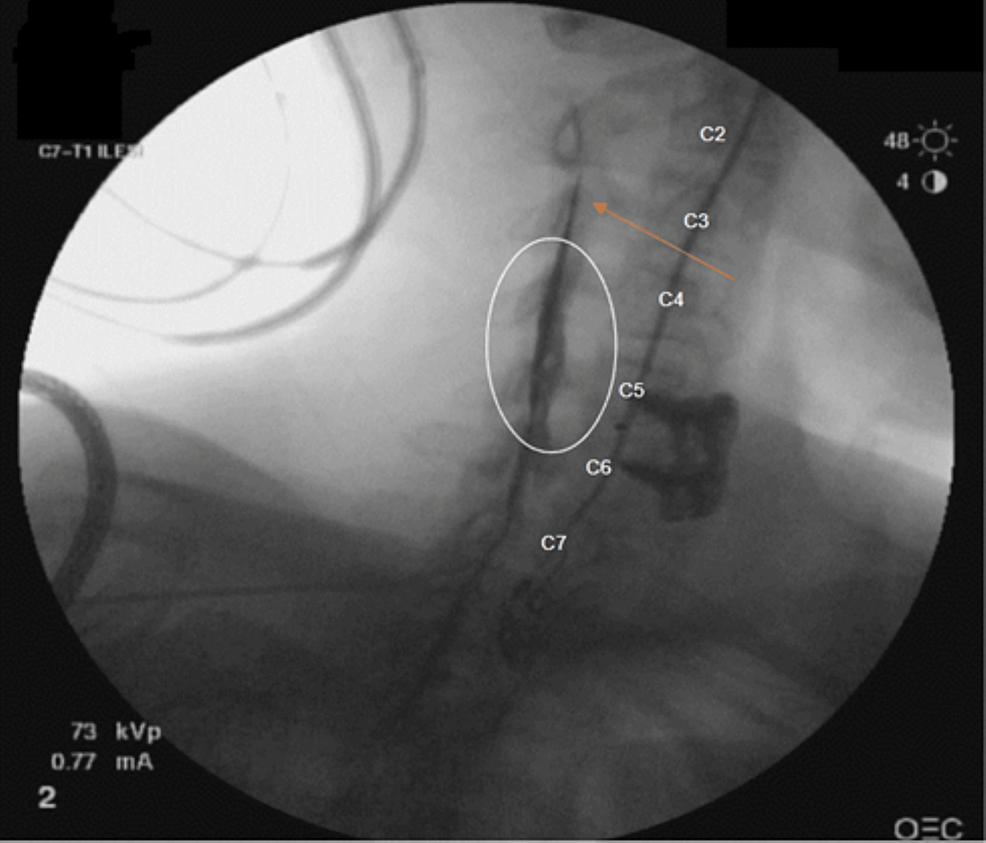

Interlaminar (A) and transforaminal (B) epidural injections at the C67 Catheter Epidural Steroid Injection The medications used are typically a numbing medication combined with an opioid and instead of a quick shot, a catheter is placed in the intrathecal space to deliver. One of our physicians will use a catheter. Local anesthetic and steroid mixtures injected into the epidural space are used to provide pain relief in patients with lumbosacral radiculopathy. Catheter guided injections. Catheter Epidural Steroid Injection.

(PDF) Epidural Catheters for Cervical Epidural Steroid Injections to Catheter Epidural Steroid Injection Catheter guided injections allow for an epidural injection to be accurately placed at any given level in the epidural space of the spine. It’s a catheter that is inserted into your “epidural space,” using a needle, which is right outside of the membrane that protects. The medications used are typically a numbing medication combined with an opioid and instead of. Catheter Epidural Steroid Injection.

CatheterAssisted Cervical Epidural Steroid Injection Catheter Epidural Steroid Injection Local anesthetic and steroid mixtures injected into the epidural space are used to provide pain relief in patients with lumbosacral radiculopathy. The medications used are typically a numbing medication combined with an opioid and instead of a quick shot, a catheter is placed in the intrathecal space to deliver. Catheter guided injections allow for an epidural injection to be accurately. Catheter Epidural Steroid Injection.

Cureus Epidural Catheters for Cervical Epidural Steroid Injections to Catheter Epidural Steroid Injection The medications used are typically a numbing medication combined with an opioid and instead of a quick shot, a catheter is placed in the intrathecal space to deliver. Catheter guided injections allow for an epidural injection to be accurately placed at any given level in the epidural space of the spine. It’s a catheter that is inserted into your “epidural. Catheter Epidural Steroid Injection.

Cureus Epidural Catheters for Cervical Epidural Steroid Injections to Catheter Epidural Steroid Injection It’s a catheter that is inserted into your “epidural space,” using a needle, which is right outside of the membrane that protects. Local anesthetic and steroid mixtures injected into the epidural space are used to provide pain relief in patients with lumbosacral radiculopathy. One of our physicians will use a catheter. Catheter guided injections allow for an epidural injection to. Catheter Epidural Steroid Injection.